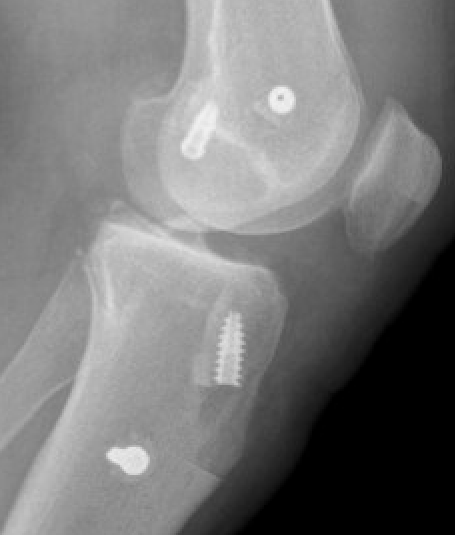

MCLRMCLRMCLR

MCLRMCLR